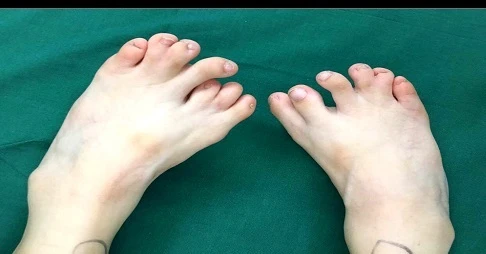

Đầu tháng 8 vừa rồi, cha mẹ bé gái đưa con họ tái khám, các bác sỹ vui mừng thông báo chân của bé gái đã phục hồi và hoạt động bình thường, không có vấn đề gì xảy ra.